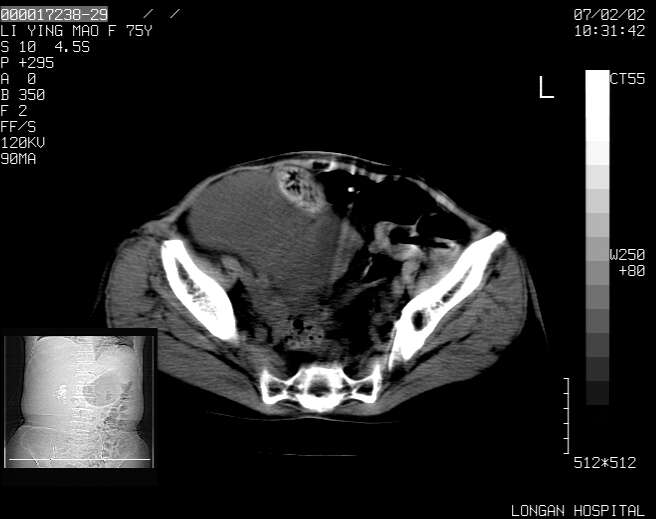

以下是引用dyqct在2007-2-10 8:53:00的发言:[br]考虑:1、肝脏多发囊肿[br] 2、左肾囊肿,右肾多发结石并积水。[br] 3、右胸少量积液。[br] 4、右肾周包裹性积液或淋巴管瘤(有见缝就钻的征象、薄隔、小结节状钙化)?[br] 5、腰椎动脉瘤样骨囊肿?[br] [br] [br]